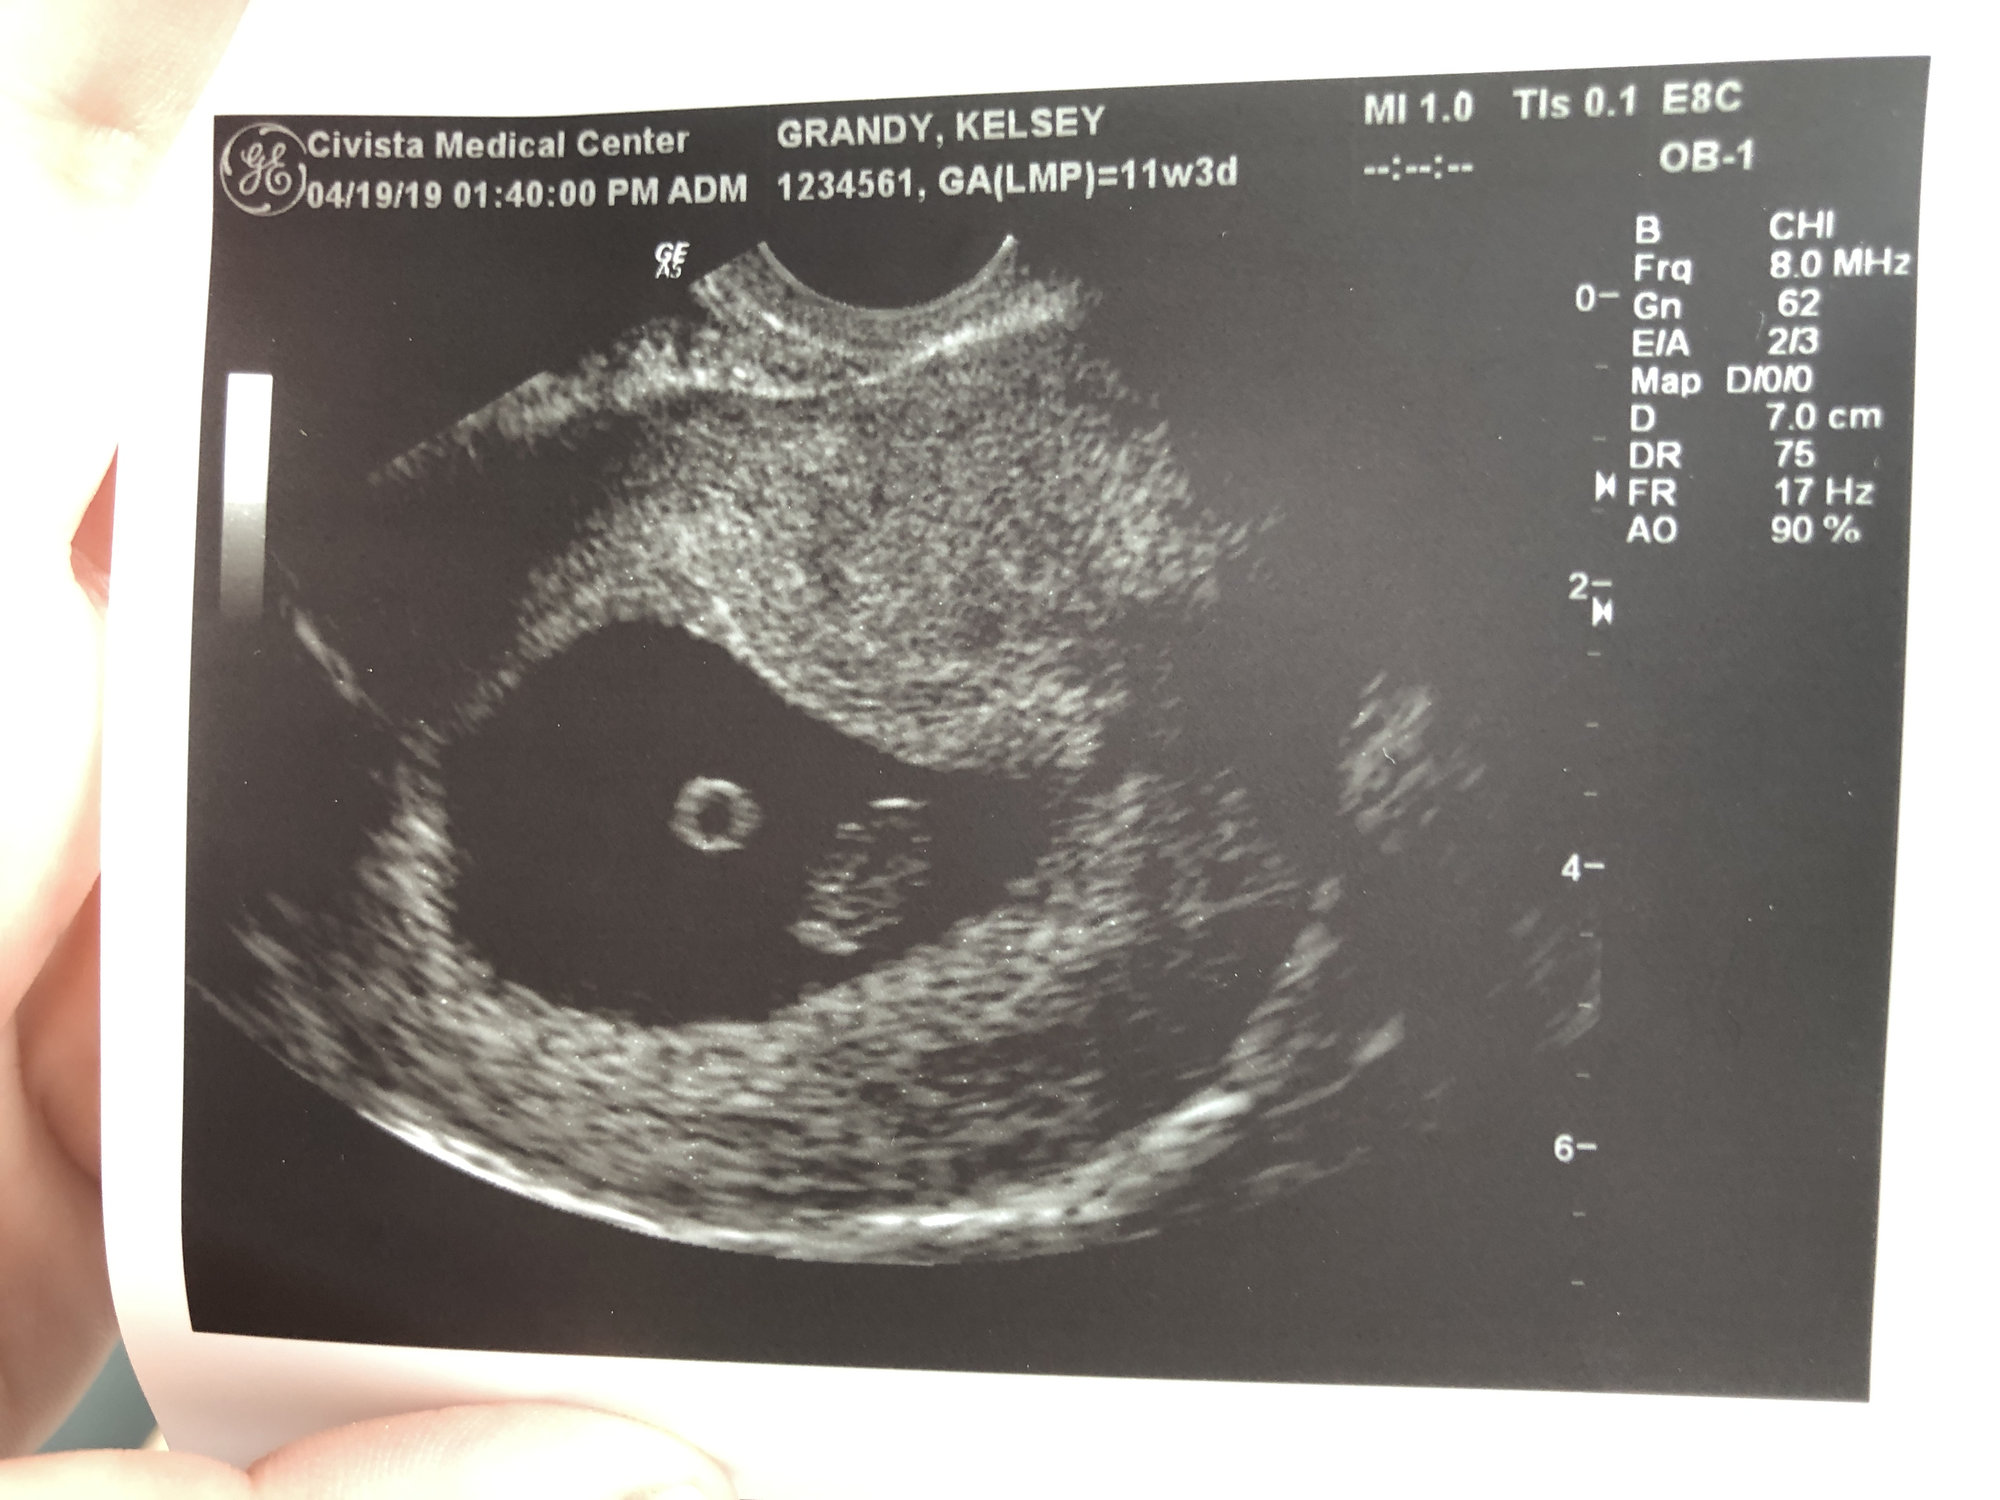

(Taken from June 2019)

Found out yesterday, I am having twins.. EDD 12.7.19